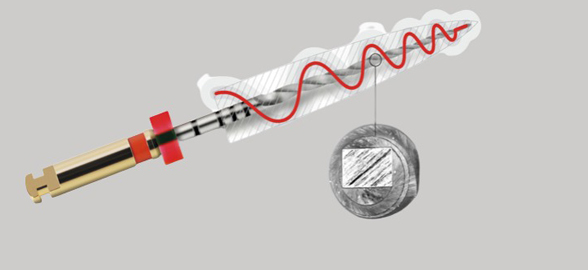

Fernando Durán, endodoncista y profesor de la Universidad de Internacional de Cataluña, nos cuenta en este video los detalles sobre el Motor de Endodoncia iRoot Pro